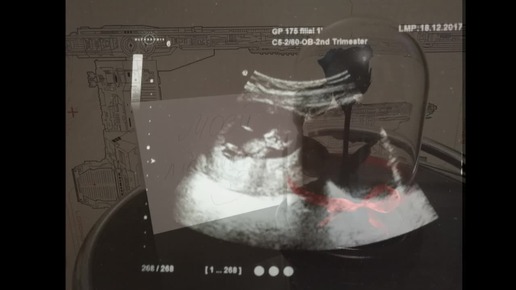

Вся беременность в одном видео